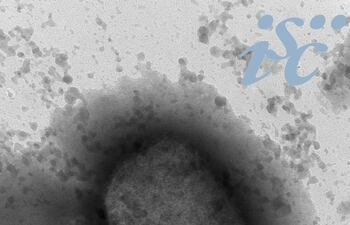

MADRID. Investigadores del Instituto español de Salud Carlos III han conseguido el primer borrador de la secuencia completa del virus causante de la viruela del mono (Monkey Pox) que circula por España a partir de las muestras de 23 pacientes.